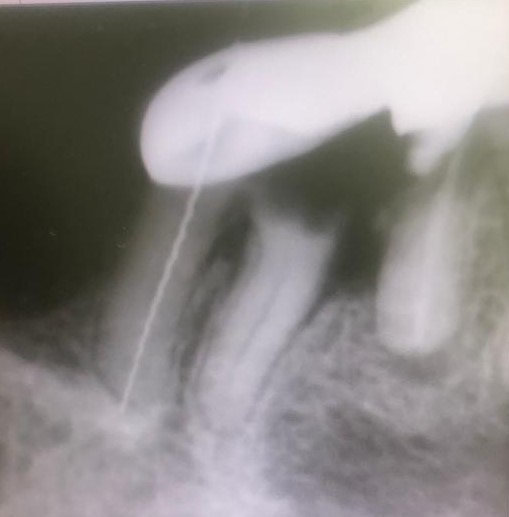

Presentamos un nuevo caso en el que la paciente presenta un gran dolor en su prótesis antigua (15 años) sobre dientes naturales tallados en zona inferior de molares. Es una paciente muy bruxómana, se unieron dos molares tallados con dos coronas. En el caso que presentamos el molar anterior estaba endodonciado ya antes de colocar la prótesis fija, pero el molar distal no. Y éste era la causa del gran dolor. Esto es por haberse filtrado creando caries y destrucción dentaria que llegaba al nervio. En conclusión, produciendo una gran pulpitis.

Esto provocaba en la paciente un gran dolor, pero ella no contemplaba en ese momento la opción de levantar la prótesis para explorar las piezas que había debajo, poder visualizar la destrucción dental y rehacer todo con una prótesis nueva. Por tanto, para quitar el dolor normalmente habría que haber hecho las extracciones de los dos molares, lo cual sería muy invalidante. En la clínica decidimos hacer una endodoncia de la raíz distal del último molar a través de la prótesis por la zona oclusal, y hacer odontosecciones de las raíces lesionadas sin quitar la prótesis. Ésta va permanecer tal como estaba.

Lo cierto es que las raíces  ya estaban bastante separadas de el resto de los molares correspondientes por su destrucción, lo que nos permitió la extracción de estas raíces en concreto. Teniendo en cuenta también que las raíces mesial y distal de cada molar no estaban unidas entre sí, sino que había una separación entre ellas.

La técnica quirúrgica para este menester es parecida a una apicectomía, pero en lugar de quitar solo el ápice radicular quitamos toda la raíz dental. Así pues lo que se hizo fue extracción de la raíz distal del primer molar y extracción de la raíz mesial del segundo molar. Con lo que la prótesis sigue teniendo dos pilares.

Con la secuencia de imágenes se comprende muy bien la técnica quirúrgica realizada.